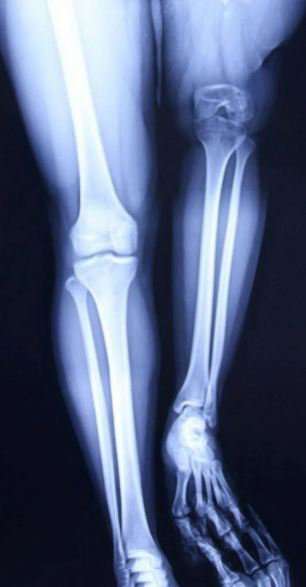

Չինաստանում երիտասարդ կնոջ ձախ ոտքը երկարացրել են 23 սանտիմետրով: 21-ամյա Սյույ Հուանը դեռ երեխա ժամանակից տառապել է ոսկորների վարակով: Նրա ազդրի ոսկորն ախտահարված է եղել մանրէներով:

Այդ պատճառով աղջկա ձախ ոտքն աջից 23 սանտիմետրով կարճ է եղել, իսկ դա նշանակել է, որ նա իր կյանքի մեծ մասը պետք է հենակների օգնությամբ տեղաշարժվեր:

«Նրա վիճակը շատ ծանր էր: Ոչ միայն աղջկա ոտքն էր կարճ, այլև նրա ծնկի և կոնքազդրային հոդերը բավականաչափ զարգացած չէին, անհրաժեշտ էր դրանք փոխարինել»,- ասում է վիրաբույժ Հու Յուհը: